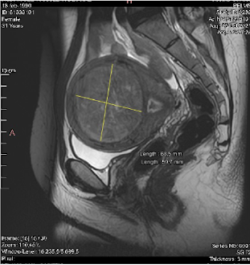

- El tamaño y localización de los miomas (ver clasificación de la FIGO)

De hecho, todos los miomas del 0 al 6, son candidatos a la Radiofrecuencia.

- Miomas tipo 0, 1 y 2, que llegan incluso a ocupar toda la cavidad interna del útero, producen aumento en el sangrado menstrual, tanto en la cantidad como en la duración, que llega a precisar en ocasiones transfusiones sanguíneas.